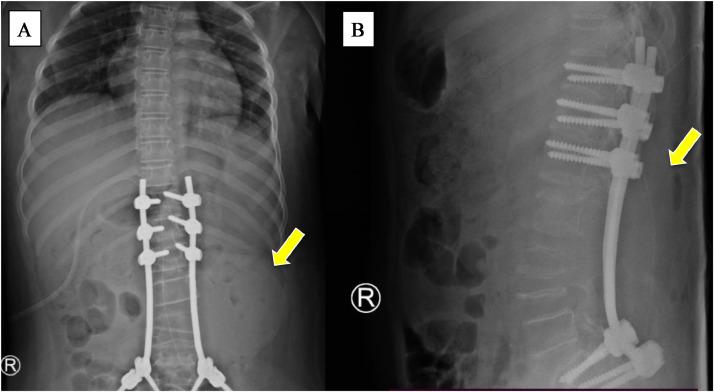

Aneurysmal bone cyst (ABC) is a benign and locally proliferative vascular disorder in the form of a non-neoplastic bone lesion commonly found in children and young adults. Several treatments and therapeutic options are available. Percutaneous sclerotherapy is an alternative treatment for ABC with less morbidity than other therapies. An 11-year-old girl presented with a lump in her left flank since 10 months ago with paresthesia, and leg weakness. The patient was unable to raise her legs and walk. The patient underwent posterior surgical and stabilization procedures with tumor extirpation. Three months postsurgery, the lump progressively increased and tenderness. MRI showed an expansile destructive lytic lesion, firm borders, regular margins, and multiple septa with clear transition zones, without periosteal reactions, forming a picture of a "soap bubble appearance" surrounding the lumbar paravertebral. The patient underwent sclerotherapy using 5 ml of absolute alcohol under visual fluoroscopy guidance. After the sclerotherapy, the patient showed clinical improvement and decreased lump size. No side effects or massive bleeding were experienced postsclerotherapy. Thoracolumbar x-ray post sclerotherapy showed a decreased mass size in the posterior lumbar area. This case demonstrates that sclerotherapy presents a secure alternative for pediatric patients in contrast to spinal ABC surgery. It offers minimal invasiveness and reduced morbidity. The percutaneous administration of absolute alcohol proves effective in treating spinal ABC. In this case, the patient experienced clinical improvement, leading to a decrease in lump size. There were no instances of significant bleeding around the lump postsclerotherapy.

动脉瘤样骨囊肿(ABC)是一种良性的、局部增生性血管疾病,表现为非肿瘤性骨病变,常见于儿童和年轻人。有多种治疗方法和治疗选择。经皮硬化治疗是ABC的一种替代治疗方法,其发病率低于其他治疗方法。一名11岁女孩自10个月前起左腰部出现肿块,并伴有感觉异常和腿部无力。患者无法抬腿行走。患者接受了后路手术及稳定手术并切除肿瘤。术后3个月,肿块逐渐增大且有压痛。磁共振成像(MRI)显示一个膨胀性溶骨性破坏病变,边界清晰,边缘规则,有多个分隔,过渡区清晰,无骨膜反应,形成腰椎旁“肥皂泡样外观”。患者在透视引导下使用5毫升无水乙醇进行硬化治疗。硬化治疗后,患者临床症状改善,肿块大小减小。硬化治疗后未出现副作用或大量出血。硬化治疗后的胸腰椎X线片显示腰椎后部区域肿块大小减小。该病例表明,与脊柱ABC手术相比,硬化治疗为儿科患者提供了一种安全的替代方法。它具有微创性且发病率降低。经皮注射无水乙醇被证明对治疗脊柱ABC有效。在该病例中,患者临床症状改善,导致肿块大小减小。硬化治疗后肿块周围未出现明显出血情况。